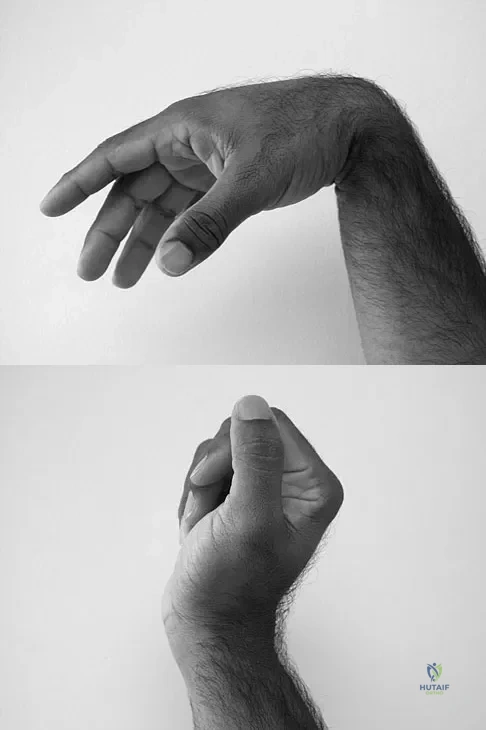

Question 53

A 35-year-old man sustained a 1-inch stab incision in his proximal forearm while trying to use a screwdriver 2 weeks ago. The laceration was routinely closed, and no problems about the incision site were noted. He now reports that he has been unable to straighten his fingers or thumb completely since the injury. Clinical photographs shown in Figures 30a and 30b show the man passively flexing the wrist. What is the most appropriate management?

Explanation